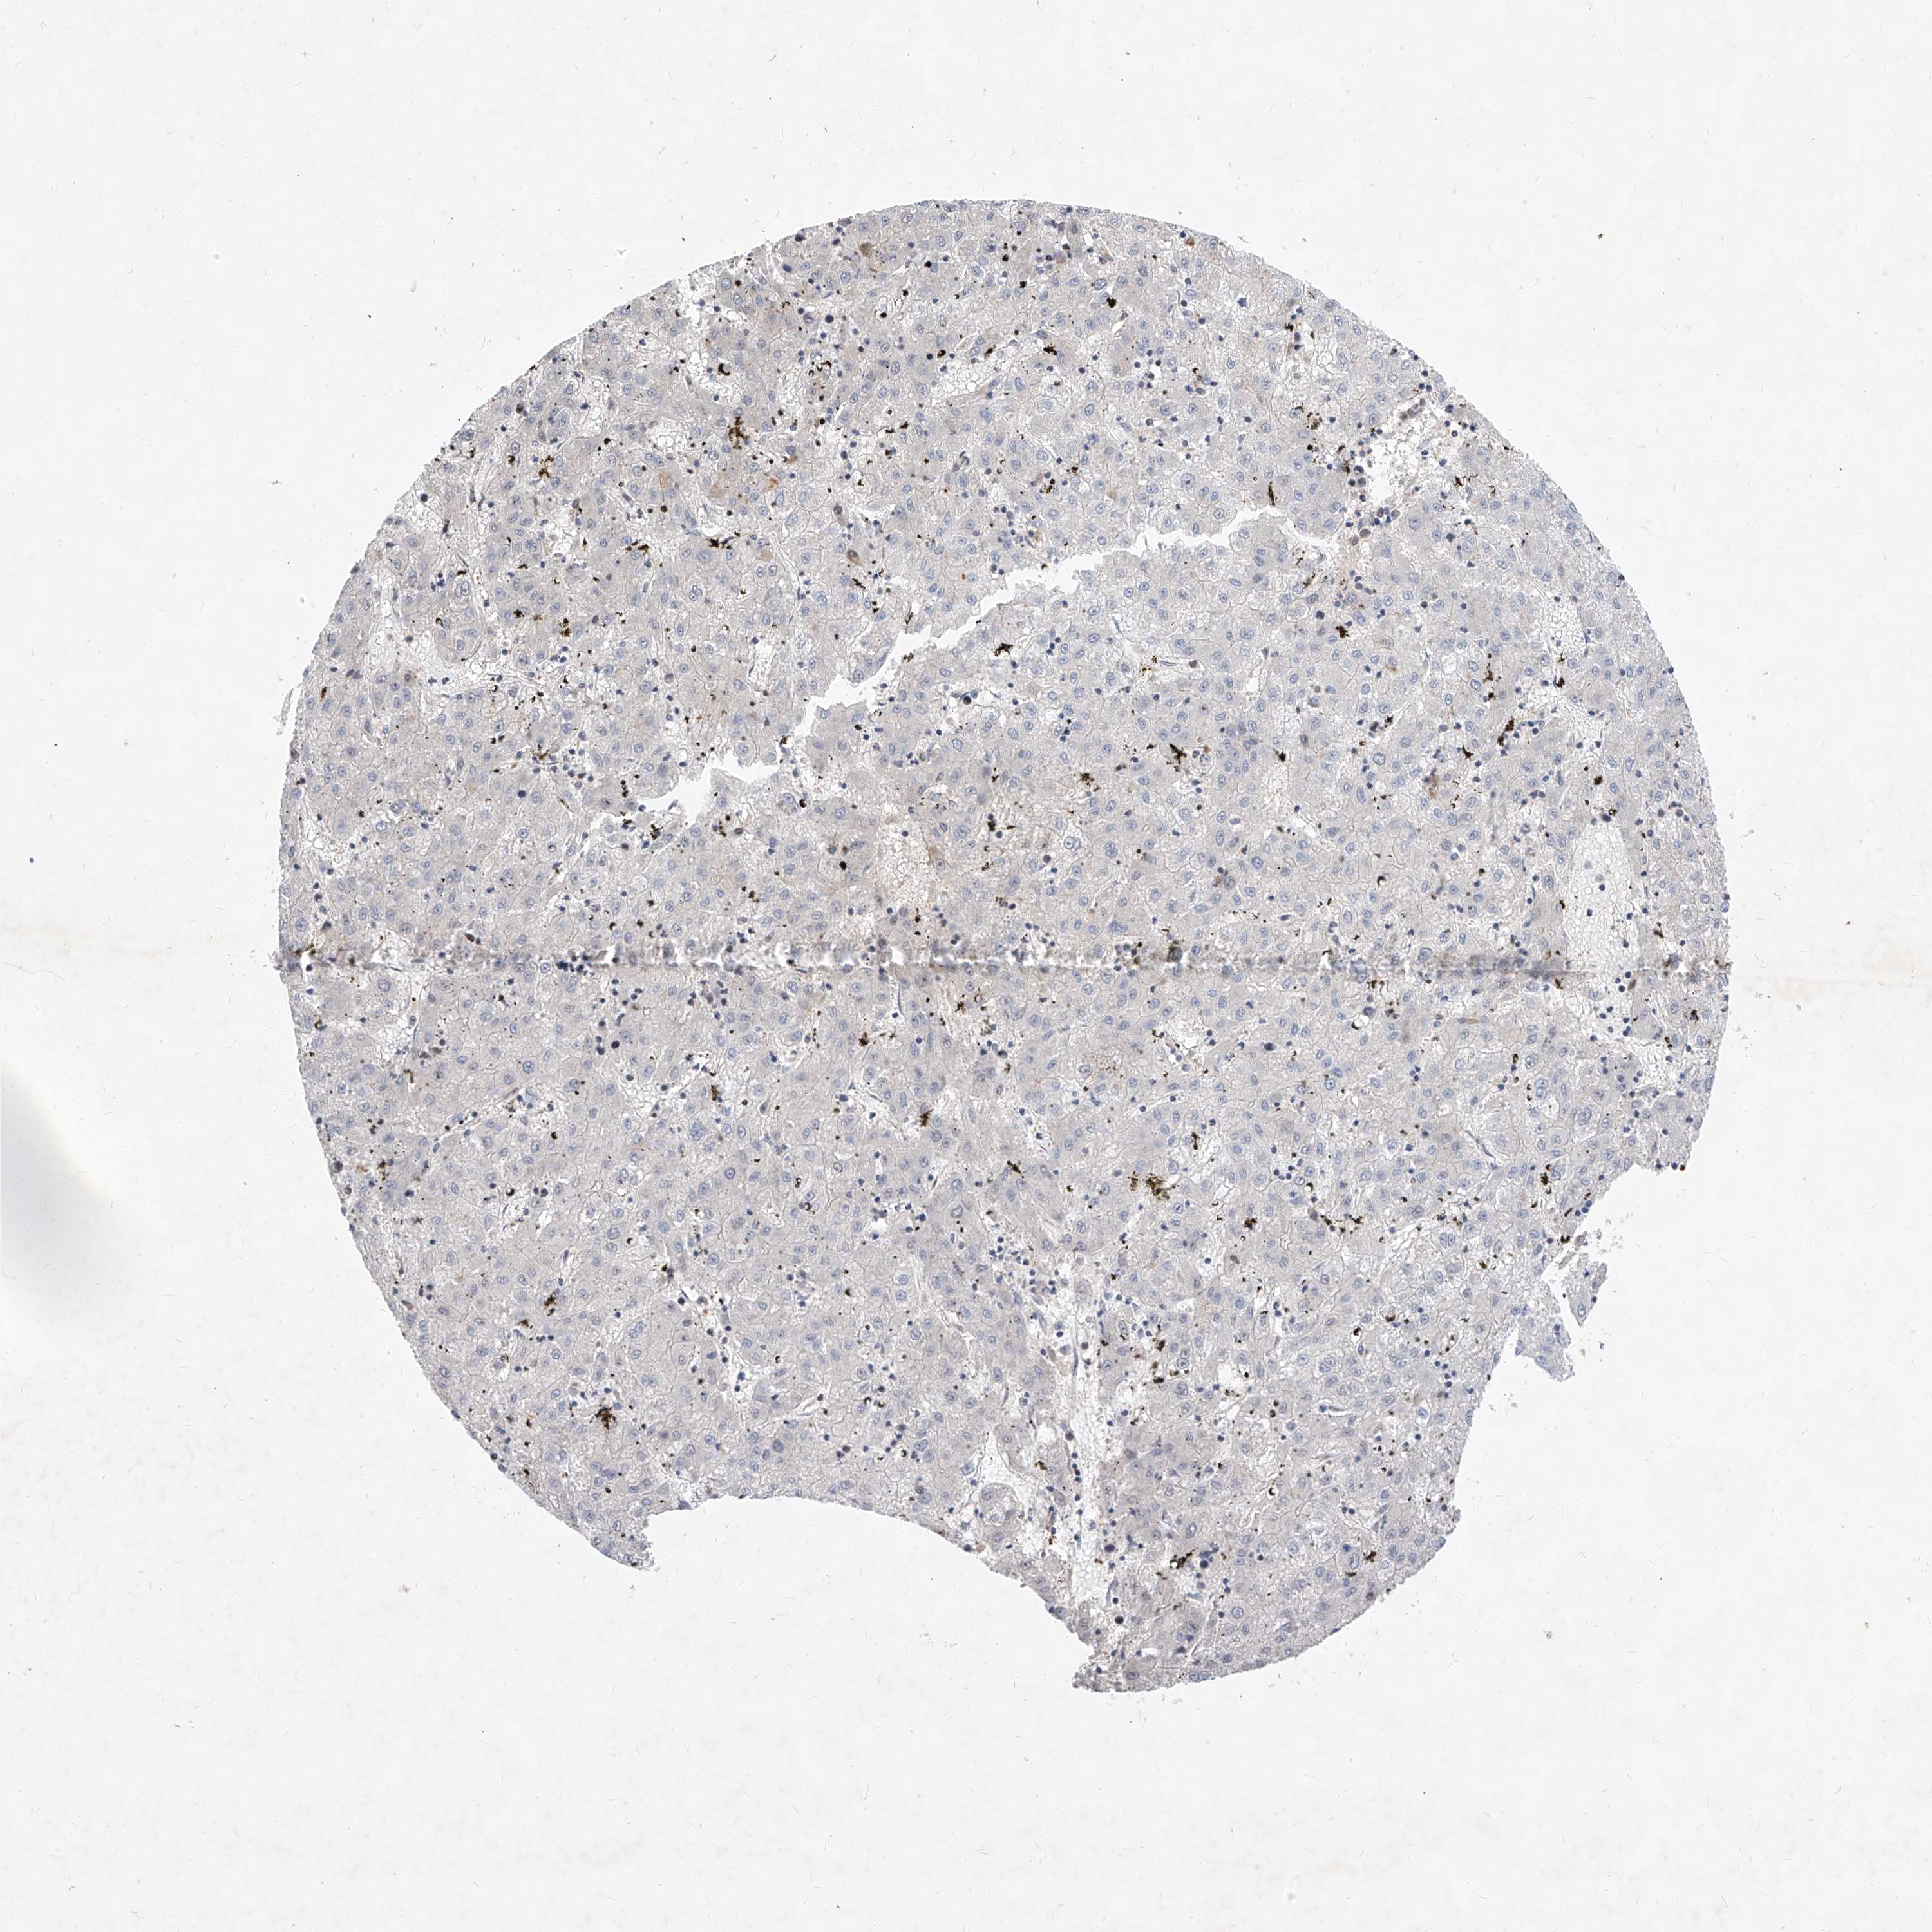

LIVER CANCER - Protein expressioni

A mouse-over function shows sample information and annotation data. Click on an image to view it in a full screen mode. Samples can be filtered based on level of antibody staining by selecting one or several of the following categories: high, medium, low and not detected. The assay and annotation is described here.

Note that samples used for immunohistochemistry by the Human Protein Atlas do not correspond to samples in the TCGA dataset.

Antibody stainingi

Antibody staining in the annotated cell types in the current human tissue is reported as not detected, low, medium, or high, based on conventional immunohistochemistry profiling in selected tissues. This score is based on the combination of the staining intensity and fraction of stained cells.

Each image is clickable and will lead to virtual microscopy that enables deeper exploration of all samples and also displays staining intensity scores, fraction scores and subcellular localization as well as patient and tissue information for each sample.

Antibody HPA030267

Staining

High

Medium

Low

Not detected

Intensity

Strong

Moderate

Weak

Negative

Quantity

>75%

75%-25%

<25%

None

Location

Nuclear

Cytoplasmic/membranous

Cytoplasmic/membranous,nuclear

Cholangiocarcinoma

Carcinoma, Hepatocellular, NOS